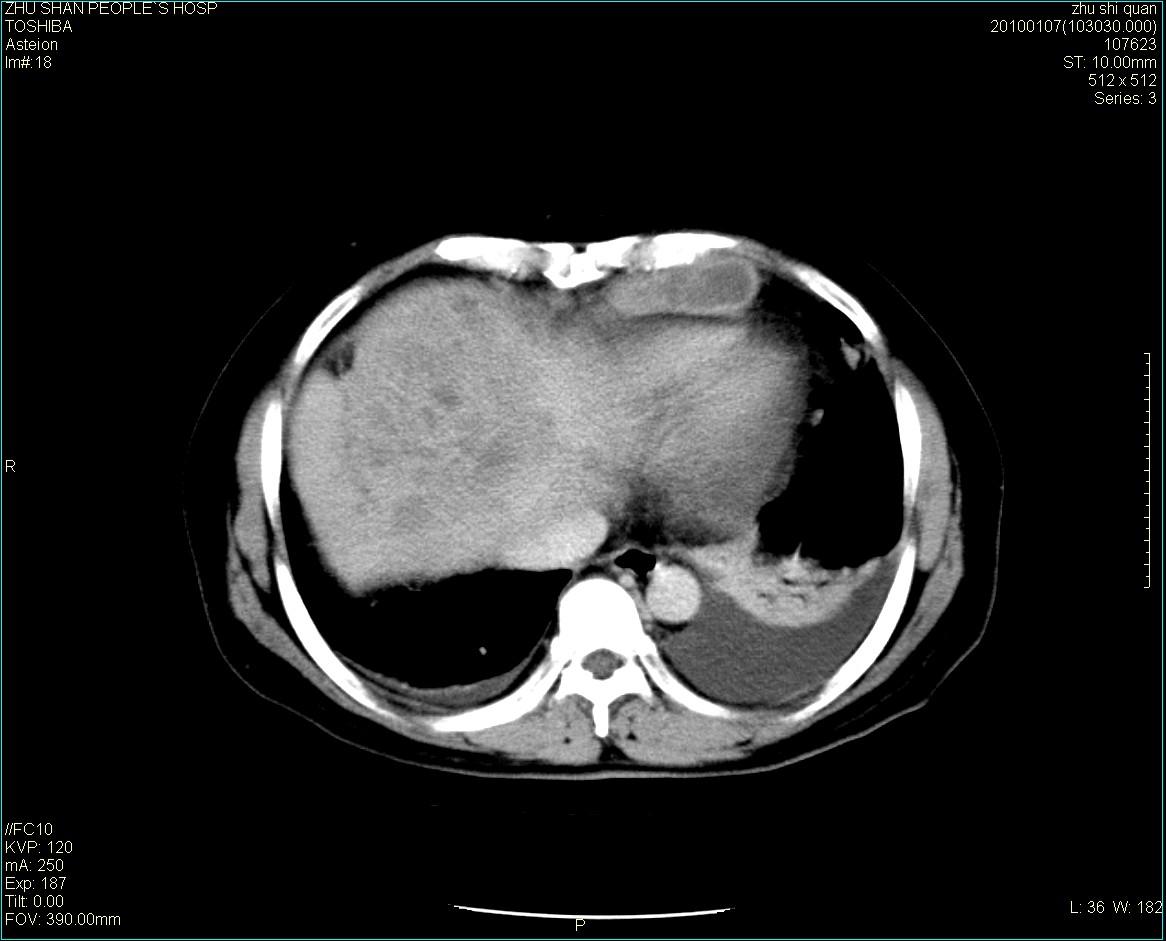

男性病人 肝ca两次术后,今日复查。

1)肝癌并多发性转移。2)双侧胸腔积液(以左侧为甚)伴左下部分肺萎陷。

肝癌术后复发,肝内、脾脏、腹膜后及腹膜多发转移,腹水,双侧胸腔积液(以左侧为甚)伴左下膨胀不全。

肝癌术后复发,肝内、脾脏、腹膜后及腹膜多发淋巴结转移,腹水,双侧胸腔积液。